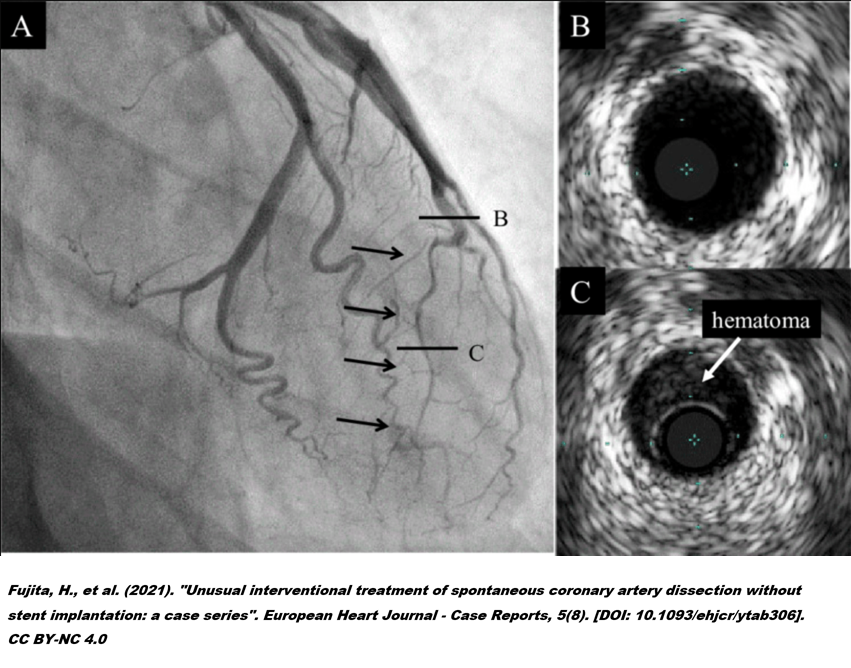

STEMI_PCI.png

13. 그래서 요즘 과학자들은 아직 숙성이 덜 된 비릿한 상태의 경화반을 구분하는 방법에 관심이 많습니다. OCT(혈관 내 촬영, Optical Coherence Tomography) 나 IVUS(혈관 내 초음파 Intravascular Ultrasound)등의 검사는 얇은 섬유막을 가진 취약 경화반을 찾는데 도움이 된다고 알려졌습니다.